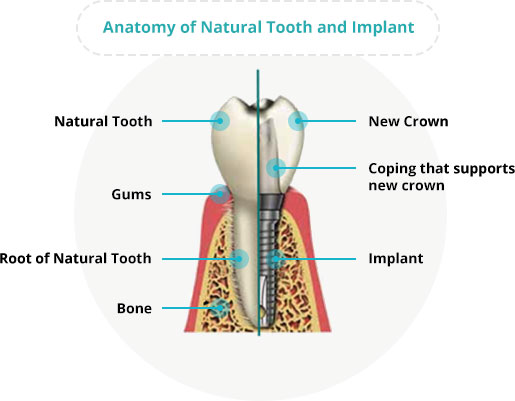

A dental implant is a small titanium screw that is surgically placed into the jawbone. It replaces the root of the missing tooth and serves as a support for your new tooth (crown) or teeth (a row of crowns, also known collectively as a bridge).

This is possible due to the biocompatible properties of titanium. A strong bond is formed between the implant and the bone over several weeks or months (osseointegration), firmly anchoring it to the jaw.

The bone around the implant heals in a process called osseointegration. The implant is considered stable when the bone grows around it and holds it in place. This healing process usually takes a few weeks to a few months, depending on your oral and overall health conditions.

By this time, the implant would have integrated with your bone and the dentist will proceed with the fabrication of replacement teeth. An abutment connects the new tooth or teeth to the implant.